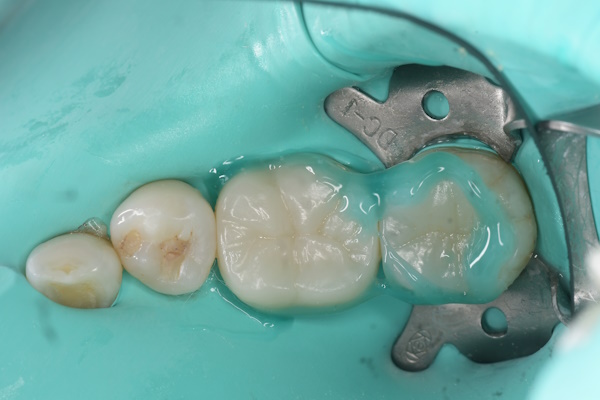

セラミック治療の治療例です。金属の使用を避けたいとのご希望から、メタルフリー治療を目的に来院されました。セラミックは生体親和性が高く、金属を使用しないため金属アレルギーのリスクが少なく、安心して使用できる素材です。当院にて虫歯治療を行い、セラミックによる修復を実施しました。通院回数の負担を考慮し、上下同時での治療をご希望されたため、同日に治療を行っています。接着の精度を高めるため、治療時にはラバーダムを使用しています。また、オキシガードは過酸化物と還元剤による化学重合反応により、歯科接着用レジンセメント表面の未重合層を硬化させる材料です。未重合層を空気から遮断することで確実な硬化を促します。

下顎

術前から術後までの治療の流れ

虫歯処置後

エッチング後

オキシガード使用後

セット後